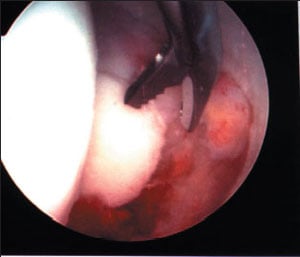

Torn labrum at rim of socket

Removal of loose body from inside the hip